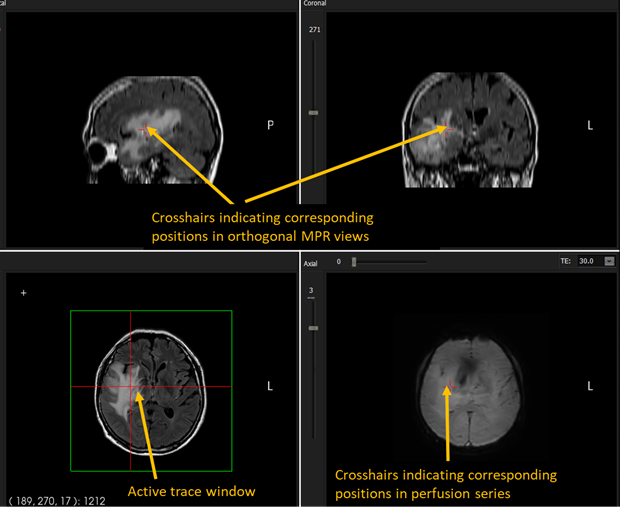

The default mode is Trace mode (left icon) whereby the current cursor position in the active MPR window is traced/updated for the same position is the orthogonal MPR views and also in the perfusion series, if present:

Figure 1: Trace mode interaction.